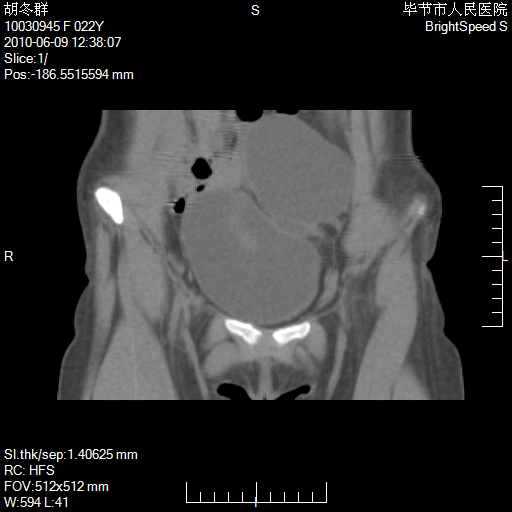

患者23岁,发现腹部包块3月。

左侧卵巢囊腺瘤或囊腺癌

盆腔内囊性占位性病变;考虑左侧卵巢囊腺瘤。

有分隔、壁薄,支持考虑左侧卵巢囊腺瘤。

左侧卵巢浆液性囊腺瘤。

有分隔、壁薄,支持考虑左侧卵巢囊腺瘤。排尿后,膀胱缩小,由于重力作用,肿块下移就到了膀胱位置,很好理解。